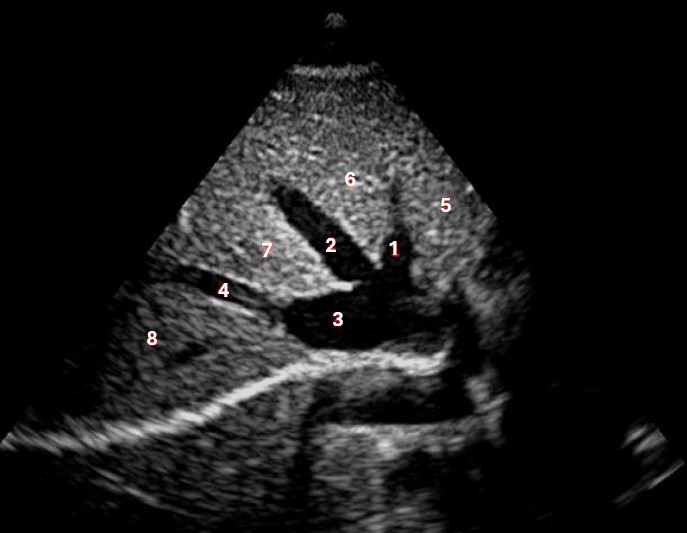

What structure/vessel is indicated by #1?

Medial branch of LPV

What structure/vessel is indicated by #2?

Left portal vein

Which of the following structures is labeled #3?

IVC

What structures/vessel is indicated by #5?

Tail of the pancreas

Which structure/vessel is indicated by #4?

Body of the pancreas

What structure/vessel is indicated by #3?

Lateral branch of LPV

What structure/vessel is indicated by #7?

Splenic vein